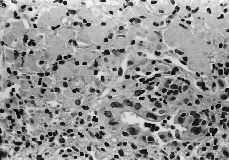

Al 15.º día del ingreso se realiza ecografía abdominal, que evidenció múltiples lesiones hipoecoicas en hígado y bazo que sugerían abscesos, aumento de ecogenicidad cortical de ambos riñones y abundante líquido libre peritoneal. Se practica ecocardiografía transtorácica que resulta normal. La biopsia hepática (Figs. 1 y 2) evidenció amplias áreas de necrosis con pericolangitis. El cultivo estándar, de Löwenstein y la tinción de Zhiel de la biop

Figs. 1 y 2.Biopsia hepática (amplias áreas de necrosis con pericolangitis).